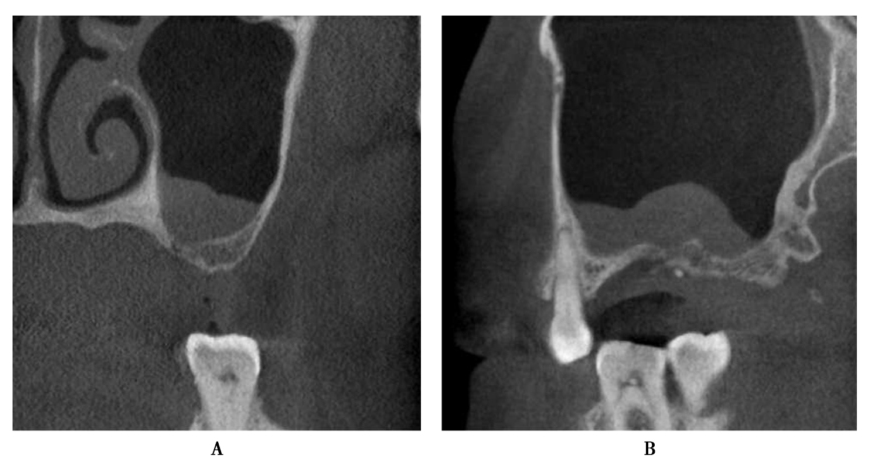

手术前CBCT检查显示患者窦腔内黏膜增厚,骨量严重不足,为保证骨增量效果,采用分期完成的方法,完成上颌窦窦底提升(图30、图31)。

图30 术前CBCT,上颌窦黏膜增厚明显A.冠状位;B.矢状位

图31 上颌窦外提升术后,CBCT显示植入的骨粉及增厚的黏膜情况A.矢状位;B.冠状位